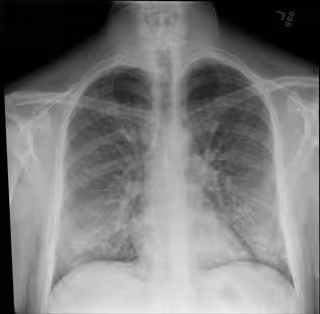

Radiografía de tórax

Radiografía de tórax - INTERMOUNTAIN HEALTHCARE - Archivo